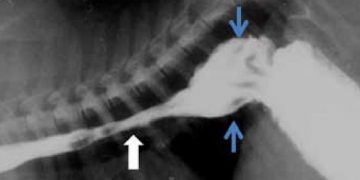

Yemek Borusu Divertikülümü, yemek borusu mukozasının, doğuştan veya kazanılmış nedenlerle, yerel kese tarzında genişlemesi durumudur. Özofagus divertikülümü, Özofagus divertikülü, Esophageal ...